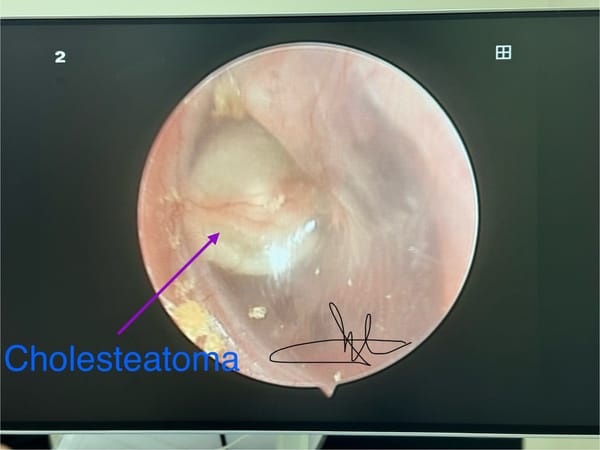

SKĐS - Cholesteatoma là khối u biểu bì lạc chỗ, thường nằm ở tai giữa hoặc xương chũm. Cholesteatoma là sự phát triển không bình thường ở lớp biểu bì da. Cholesteatoma là gì, có bao nhiêu loại? Khối Cholesteatoma có hướng phát triển như một khối u nang biểu